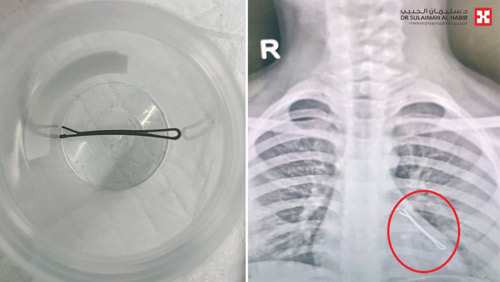

ذكر ذلك د. باسم كردي، استشاري طب الأطفال والأمراض الصدرية والمناظير الرئوية، رئيس الفريق الطبي المعالج. وقال إن الطفلة أُسعفت إلى طوارئ المستشفى، محولة من مركز طبي آخر وهي تعاني من إعياء شديد وعدم القدرة على التنفس، وفور وصولها أجريت لها فحوصات دقيقة حيث أظهرت أشعة الصدر وجود مشبك في الرئة اليسرى، فتقرر على الفور إجراء منظار رئوي لاستخراج الجسم الغريب بشكل عاجل، تجنباً لحدوث مضاعفات خطيرة.

وأضاف د. باسم: أن الطفلة خضعت لعملية عاجلة باستخدام المنظار تحت التخدير العام واستغرقت 60 دقيقة، حيث تم إدخال المنظار الرئوي الأحدث من نوعه على مستوى العالم عبر الفم دون الحاجة لأي قطع أو جراحة، وأظهر المنظار بوضوح وجود مشبك الشعر في الفص السفلي للرئة اليسرى، وتم استخراجه بنجاح، ومضت العملية بسلاسة ووفقاً للخطة ودون أية مضاعفات، وخرجت الطفلة في اليوم نفسه، وهي بصحة جيدة، ولله الحمد.